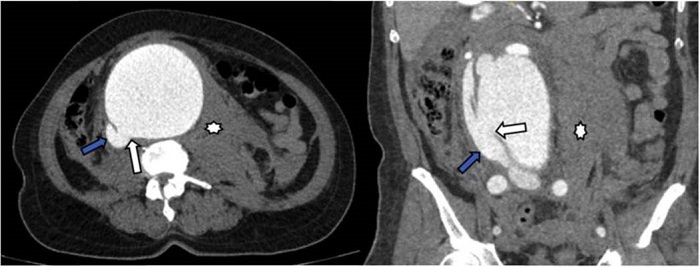

Caso clínico

Paciente de 59 años de edad con cuadro clínico de 4 días de evolución consistente en dolor lumbar irradiado a abdomen. Es remitida para valoración, sin antecedentes personales o familiares de importancia. En el examen físico, el paciente está en condiciones generales regulares, taquicárdica, con masa palpable y pulsátil a la exploración abdominal. Se procedió a la realización de angioTC de abdomen. En la fase arterial se observó dilatación aneurismática de la aorta abdominal infrarrenal con un alcance de diámetro de hasta 94 mm con comunicación de la luz entre la aorta abdominal y la vena cava inferior sugestivo de fístula aortocava (Figura 1).

Opacificación temprana de la VCI en la fase arterial 8.

Pérdida de los planos grasos entre la aorta y la VCI 8.

Aumento del diámetro de la VCI 8.

Visualizar la comunicación anormal entre la aorta y la vena cava 6.

Signos adicionales que soportan FAC son la hipoperfusión renal y la ruptura del aneurisma 5. El trabajo de Navdeep Singh y colaboradores concluyó que la presencia simultánea de contraste en la aorta y la VCI durante la fase arterial es el signo diagnóstico más importante; sin embargo, muy a menudo el aneurisma comprime la VCI, lo que dificulta la evaluación de este signo 5.